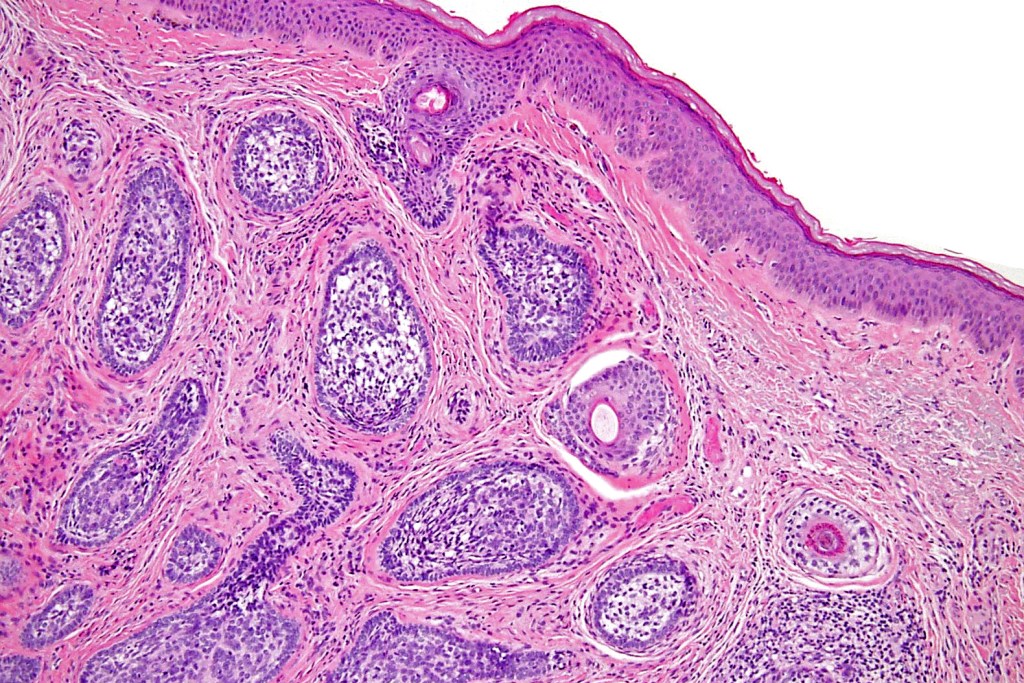

Histological features

•Dermal nodule, rarely extends into subcutaneous fat

•Irregular lobules of epithelial cells embedded in a dense fibrous stroma

•Peripheral rim of darkly staining basaloid cells surrounding larger pale staining cells with vesicular nuclei with often prominent eosinophilic nucleoli

•No retraction artifact or stromal mucin

•Admixed lymphocytes (an obligatory feature)

•Germinal centers sometimes present

•+/- focal sebaceous differentiation (rare)

•+/- focal ductal differentiation (rare)